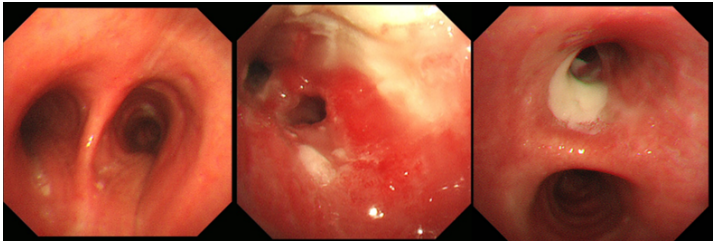

【2023-02-20】纤维支气管镜(图6):左、右支气管较多脓性分泌物,左上叶开口处见脓苔附着,开口狭窄,碰之易出血;右上叶予以灌洗,送检培养、结核菌;同时在镜下于左、右上叶局部两性霉素B 5 mg/50 ml喷洒治疗。

图片

图6  纤维支气管镜检查2023-02-20)